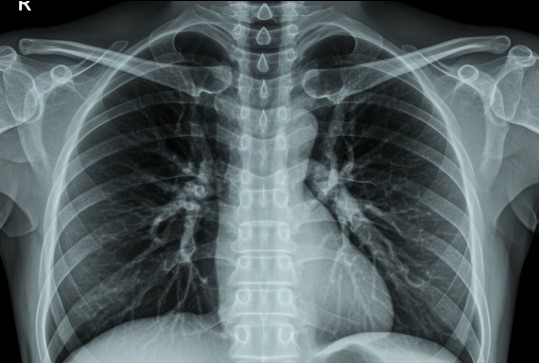

폐 건강을 위한 정기 검진의 중요성 🏥

평소에는 아무 증상이 없지만, 조용히 진행되는 폐 질환도 많습니다.

그래서 더욱 중요한 것이 바로 정기 검진입니다.

✅ 폐 기능 검사(FVC, FEV1)를 통해 폐활량과 호흡 속도를 측정할 수 있어요.

✅ 흉부 X-ray 검사로 폐렴, 결핵, 종양 등 이상 유무를 확인할 수 있어요.

✅ 흡연자라면 더욱 주기적인 확인이 필요합니다. 건강보험공단에서도 무료 검진을 제공하니 꼭 활용해 보세요.